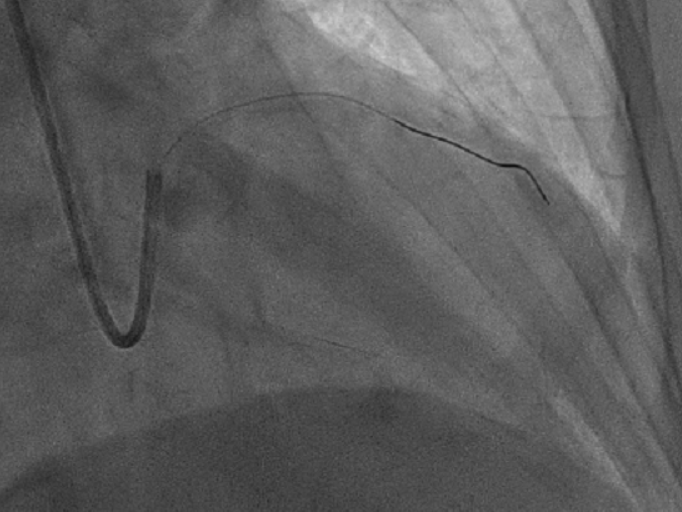

取6F SPB 3.5指引导管送入左冠口,0.014“ Comet 压力导丝校零后通过病变处送至前降支中远段,腺苷负荷后测得FFR 0.86,建议药物治疗。手术成功,拔鞘。

测量 LAD FFR:回撤压力导引钢丝,观察压力有无飘移

葛雷教授演示 Comet 压力导丝性能